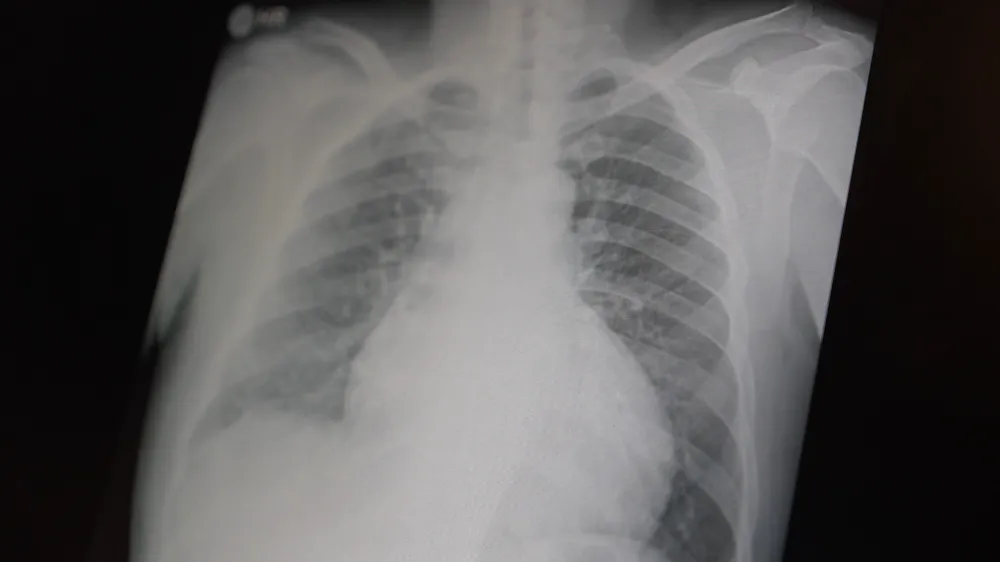

Prof. Dr. Şevket Özkaya, çocukları ve gençleri etkileyen bağımlılıklar hakkında açıklamalarda bulundu. Metamfetaminin sentetik bir uyuşturucu olduğunu ve kullanımının ölümcül sonuçlar doğurduğunu ifade eden Özkaya, "Tüm dünyada çocukları ve gençleri etkileyen iki önemli bağımlılıktan bahsetmek istiyorum. Bunlar metamfetamin ve kokain bağımlılığıdır. Metamfetamin en ölümcül, en çok bağımlılık yapan, okul çağında en kolay ulaşılabilen bir sentetik uyuşturucudur. Kullanıma bağlı ciddi akciğer ve karaciğer sorunları ortaya çıkıyor. Çok küçük dozlarda bile anında bağımlılık yapabiliyor ve tedaviyle bırakılması çok zor bir bağımlılıktır" dedi.